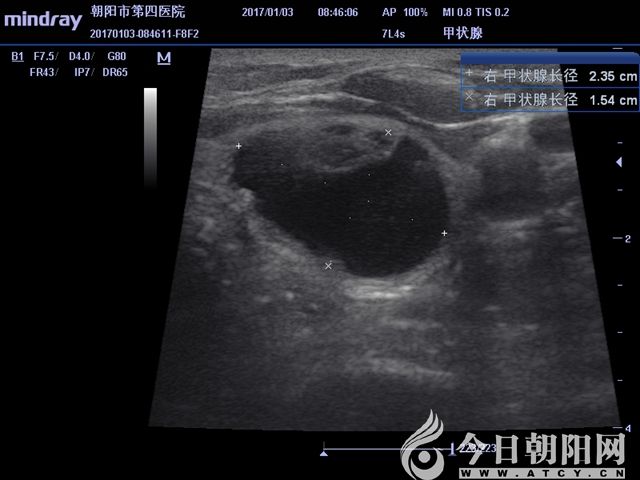

超聲顯示囊實(shí)結(jié)合性病變

超聲測(cè)得實(shí)性結(jié)節(jié)大小